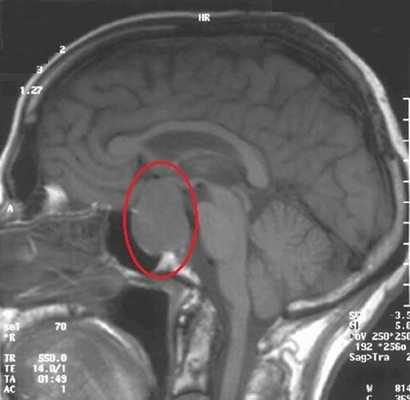

МРТ гипофиза. На МР-томограмме определяется гигантское образование неоднородной структуры (обведено) — макроаденома гипофиза.